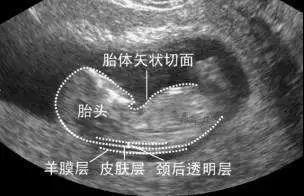

佛山都市妇产医院产科主任表示:NT检查又称颈后透明带扫描,是通过测量胎儿颈项部皮下无回声透明层较厚的部位,评估胎儿是否有可能患有唐氏综合征的一种方法,也普遍被认为和染色体异常有关。

通过B超测定颈项透明层厚度,便于及早发现唐氏儿和先天性心脏病的胎儿,并及时予以干预。它需要资深的超声科医生,配备有高档的仪器才能有效的做这个检查。

检查时由于NT的测量要求决定了B超医生必须运用B超仪器将顽皮的胎儿引导到正确的体位——正中矢状位。如果宝宝不配合,位置不好的话是测不到的。